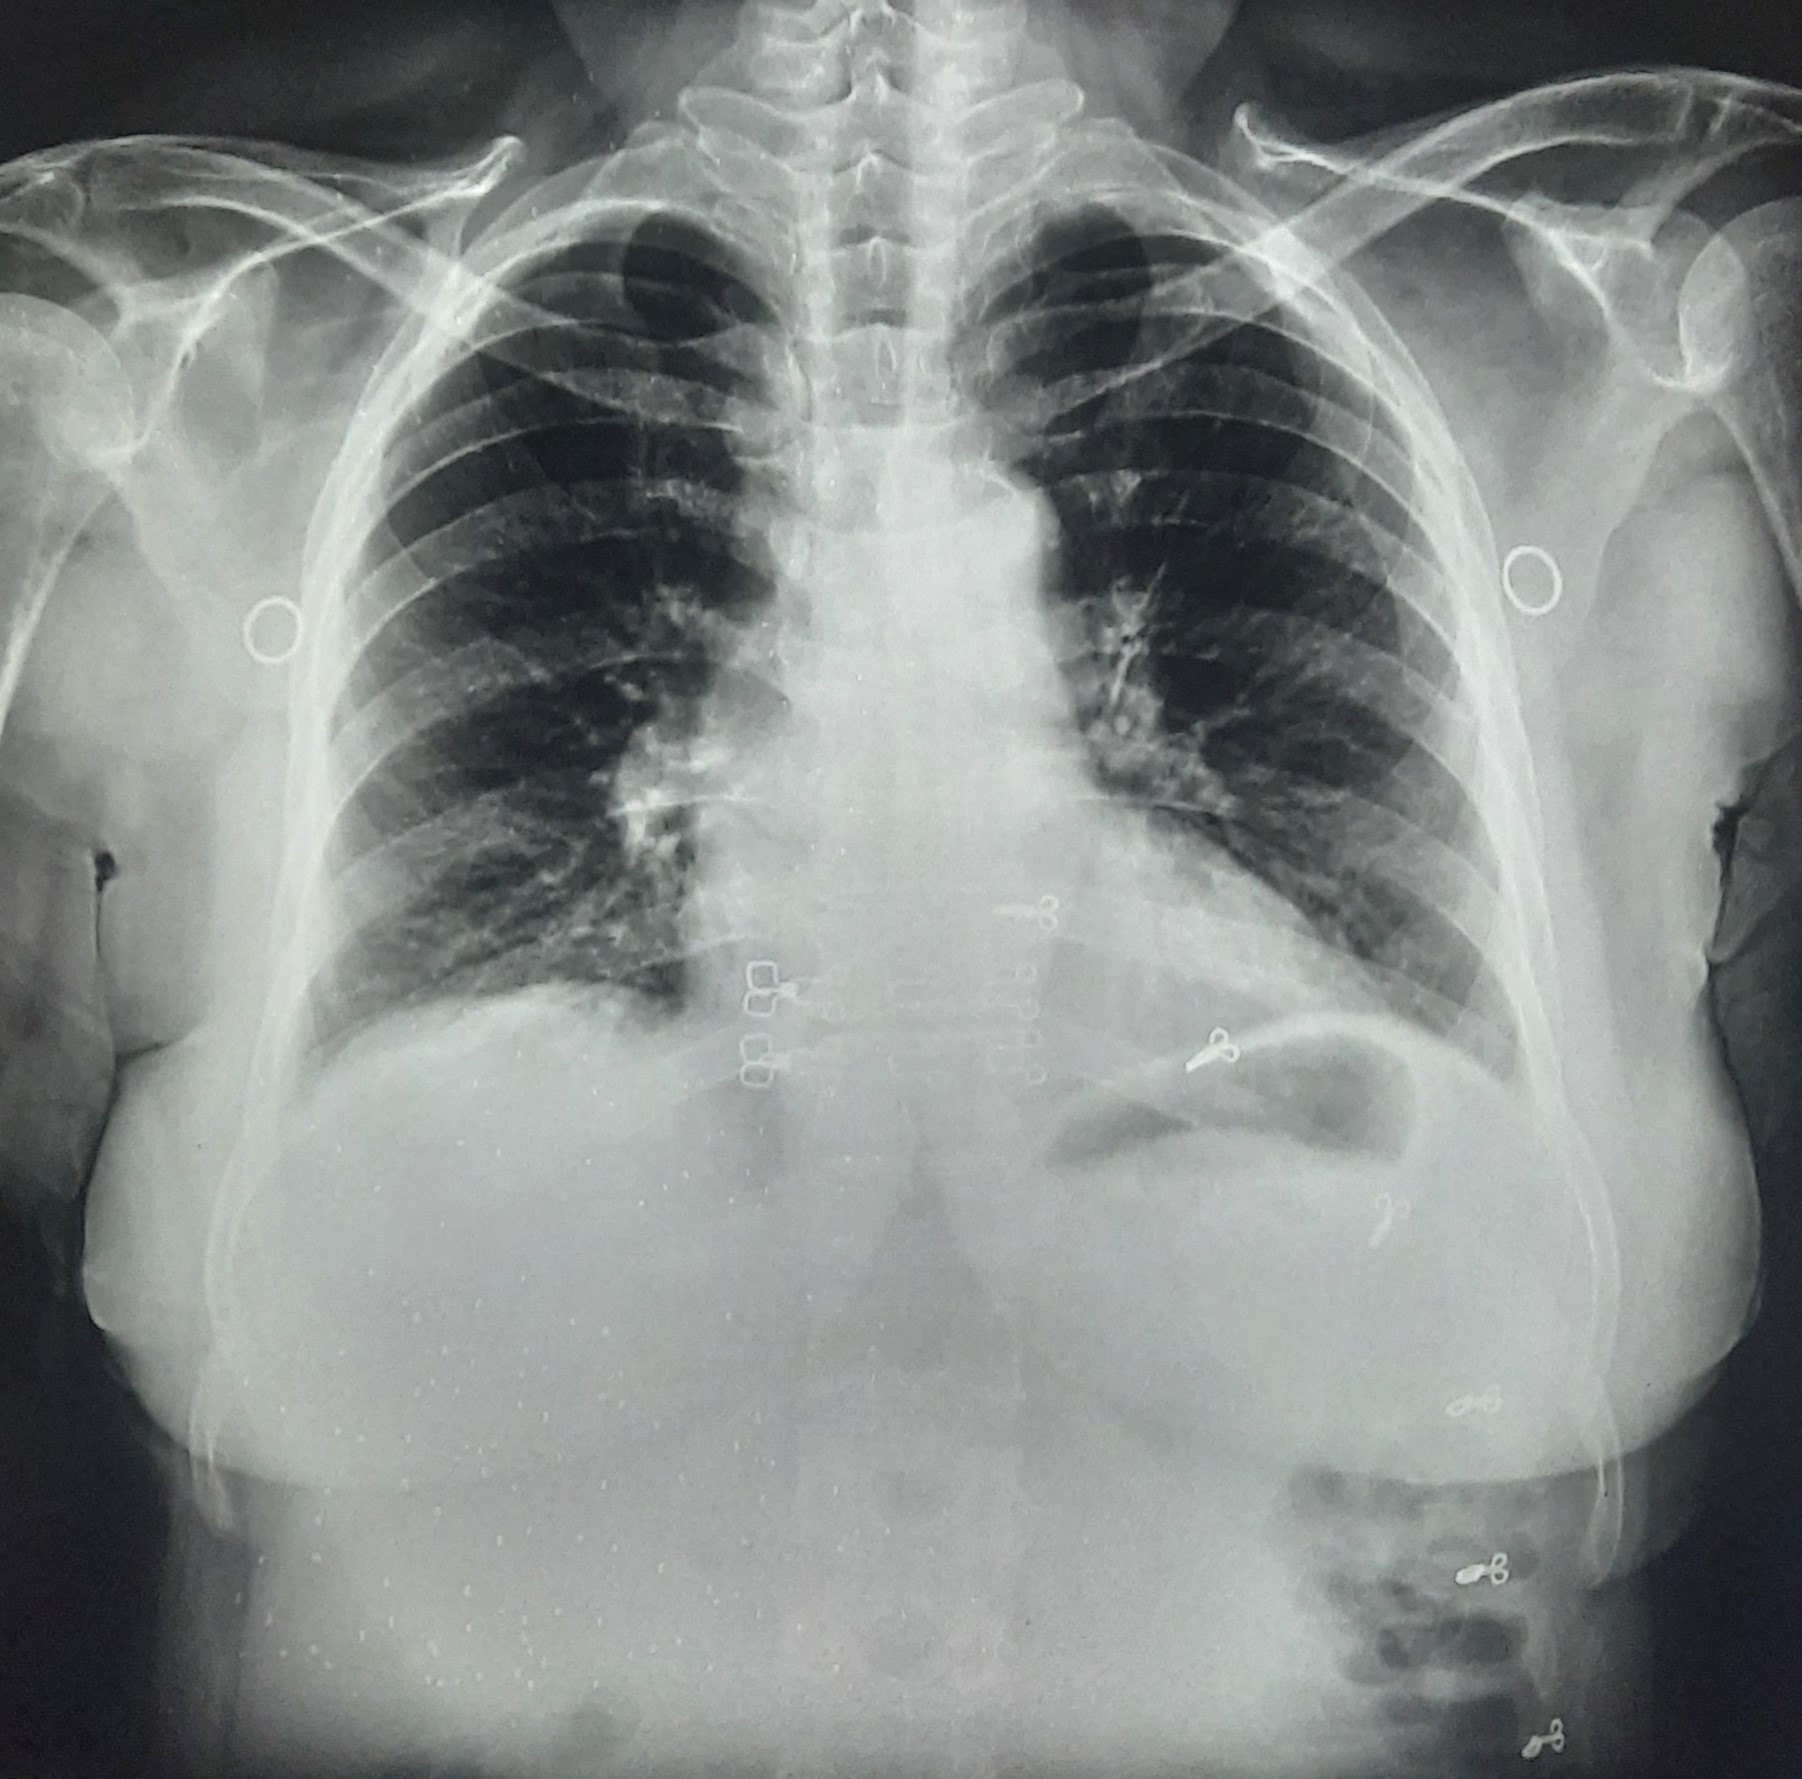

| 332 | IGGMC, Nagpur, Nagpur | P2 | 29-4140 | Mohamad Bashir | Consent taken on Paper | 75 Yrs. |

Provisional Diag : COPD

Final Diag : COPD In intense exerbation |

Non-TB Case (Confirmed) | COPD changes seen | Abnormality visible on x-ray |